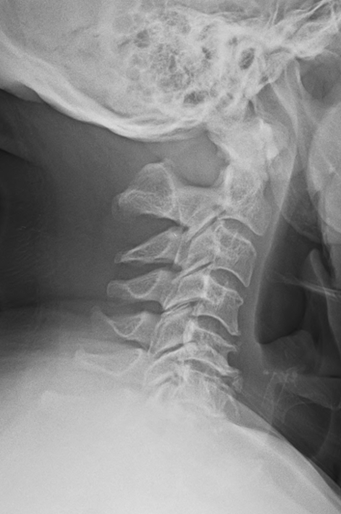

A 65-year-old male with intermittent chronic neck pain presented to his chiropractic physician’s office. He had non-specific orthopedic exam findings and a normal neurologic exam. Patient denies any history of abnormal neurologic symptoms. Radiographic examination of the cervical spine reveals complete aplasia of the posterior arch of the atlas with hyperplasia of the C2 spinous process (Figure 1). Based on the normal neurologic exam findings and no reported neurologic symptoms, no further follow-up was required.

Our patient was a morphologic type E/ clinical subgroup type 1. The question was posed if this patient was at risk for neurologic sequelae with cervical manipulation. Review of the literature suggests that the risk of cord impingement is not a factor in the morphologic group E, but that instability may occur. Therefore, before any cervical manipulation is performed, cervical flexion and extension radiographs are needed to rule out upper cervical instability. Assuming the patient is neurologically asymptomatic (particularly in extension) and no instability is present, there is no literature to suggest that cervical manipulation is contraindicated. Treatment for patients with hypoplasia of the posterior arch of the atlas should be carefully examined, properly imaged, and treated in accordance with symptoms pre- and post-manipulation (if indicated).